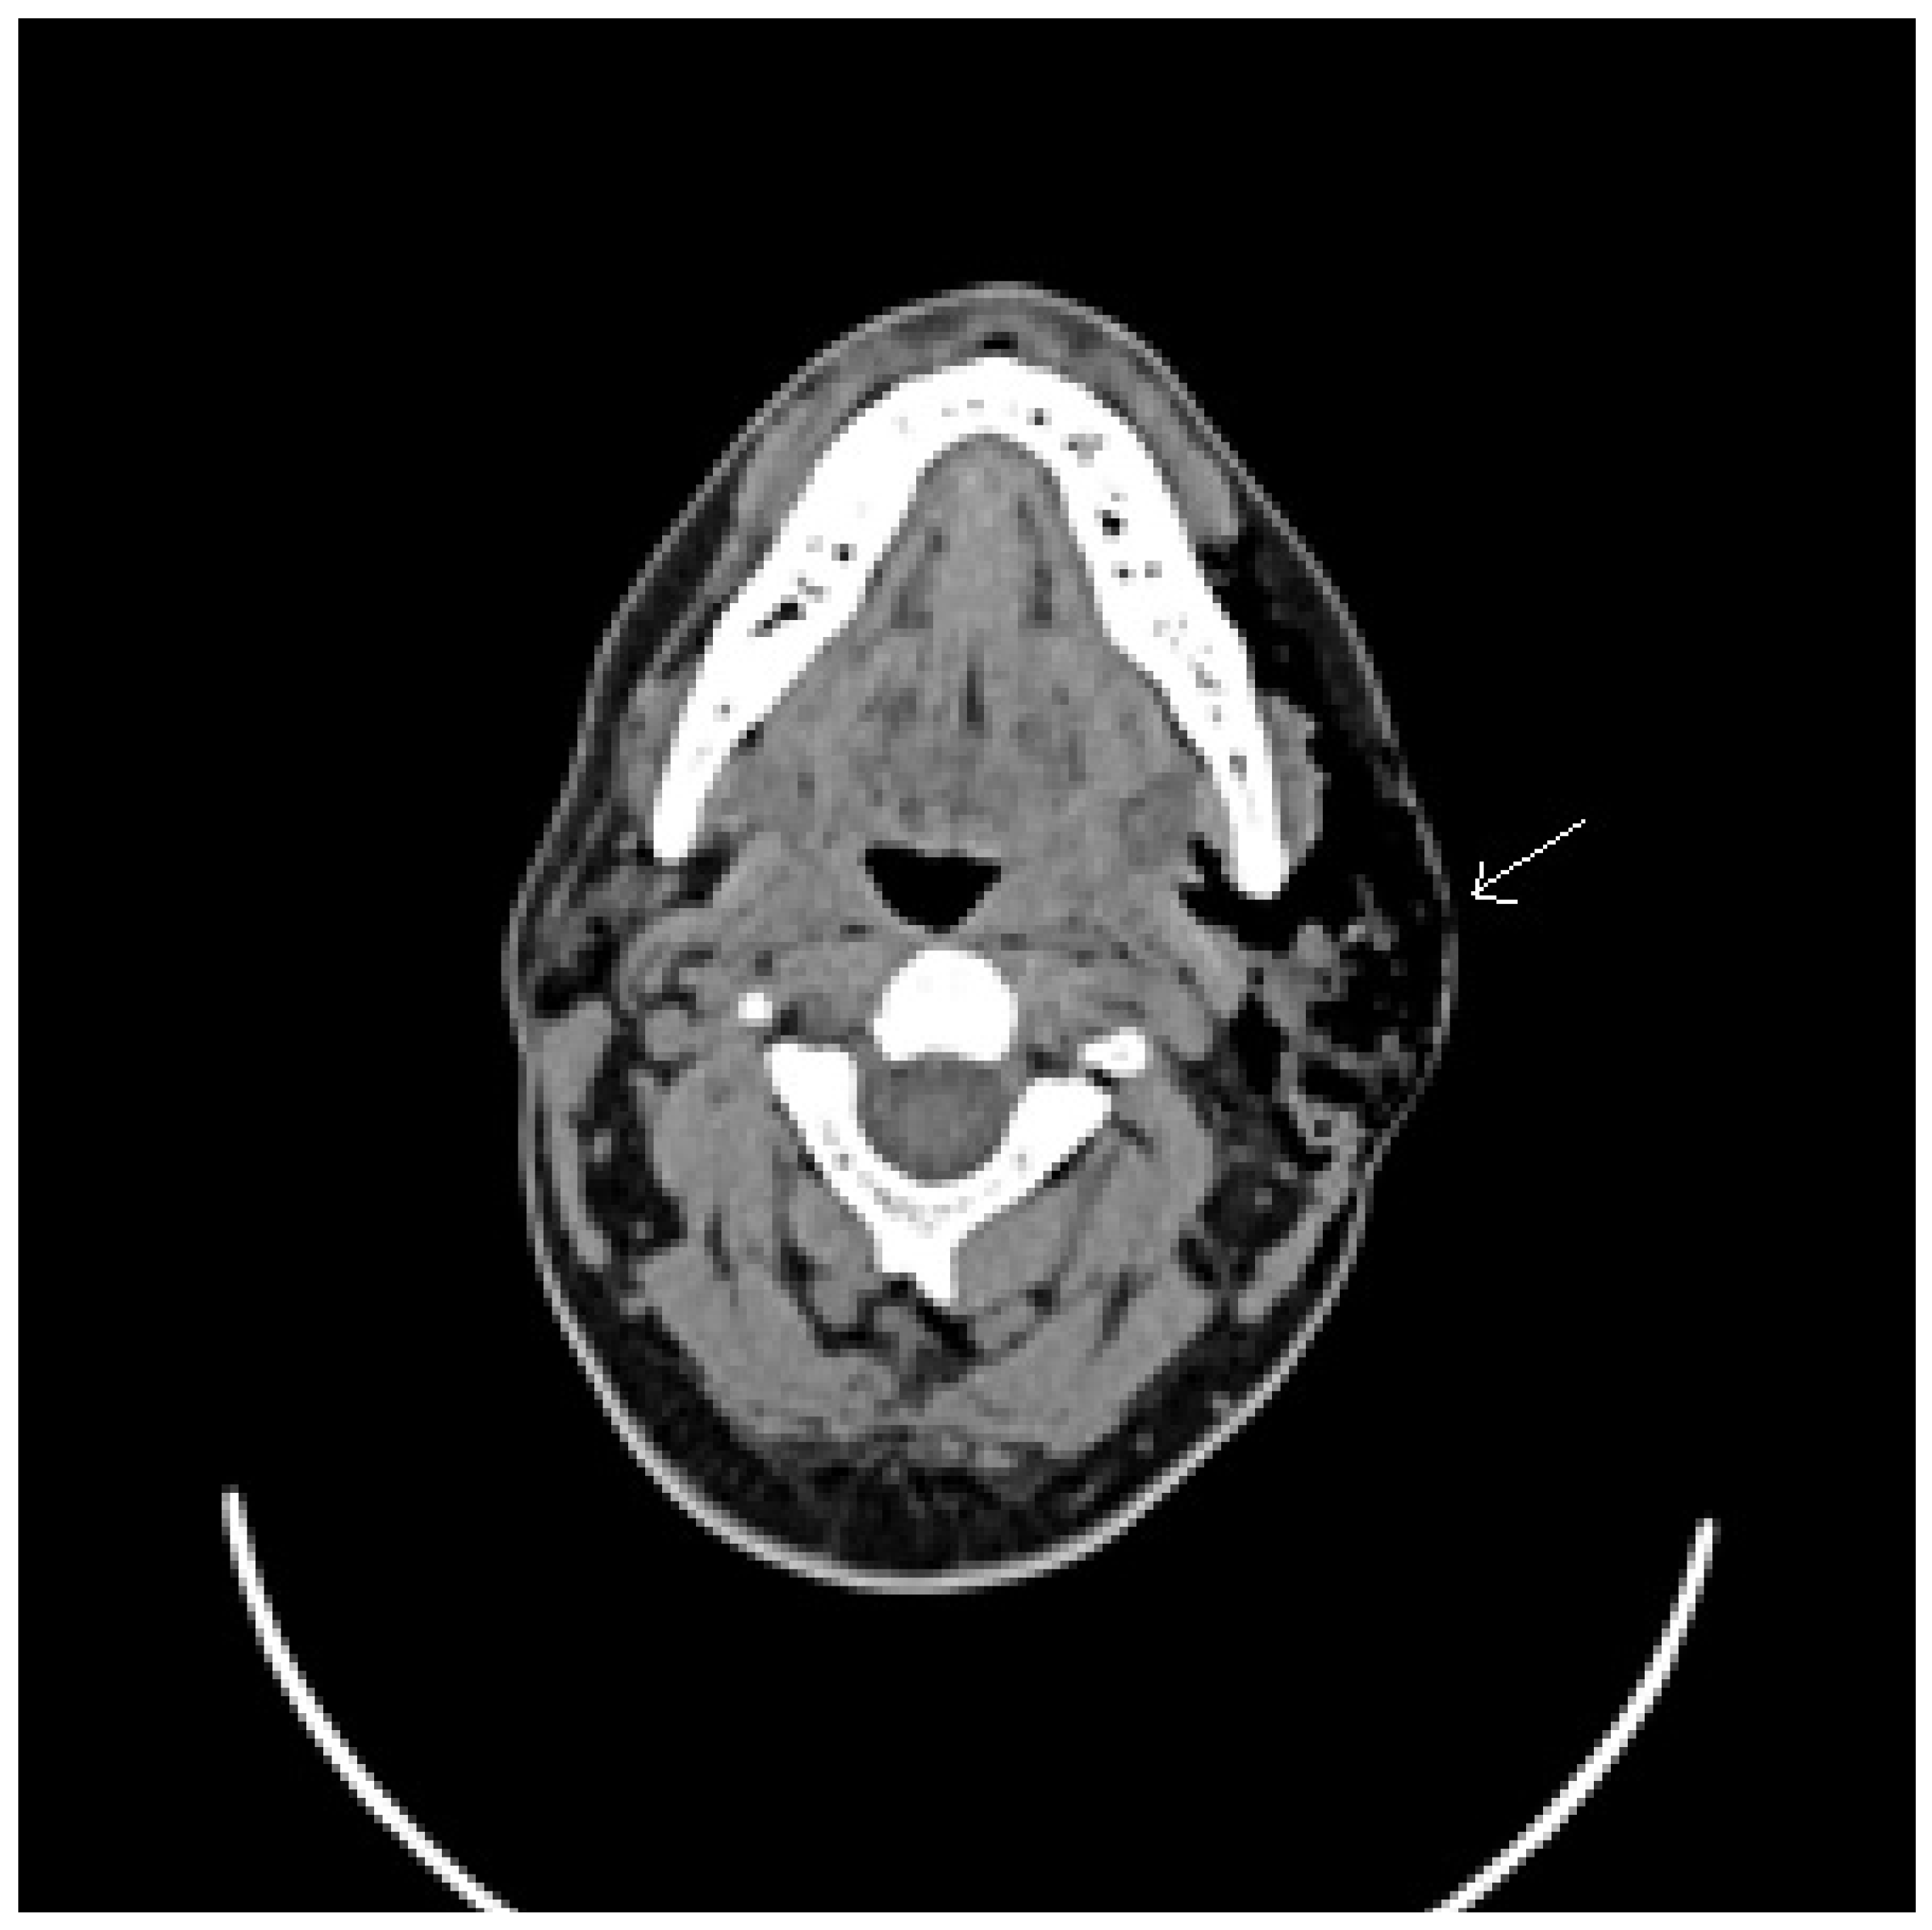

Figure 1.

Axial projection computed tomography (CT) image of a left pneumoparotid case, with the arrow indicating the presence of air in the parotid lodge.

In our experience, we report a case of a 45-year-old man with numerous episodes of painful, mono lateral left facial swelling. Clinical examination reported left-sided painful and parotid swelling with crepitus. Head–neck CT examination reported very important presence of subcutaneous emphysema that affected caudo-cranial left soft tissues from temporal region to the upper thoracic outlet, severe ectasia of Stensen’s duct, ducts of salivary glands and left parotid (Figure 1). Aware of the patient’s psychiatric conditions, psychiatric counseling is demanding. The colleagues reported that the patient suffered form of a minor cognitive disability with a tendency to somatization, underlying an important state of anxious and insomnia, prescribing a psychiatric therapy with venlafaxine, quetiapine and alprazolam. The patient is treated with antibiotic therapy and support measures with resolution of subcutaneous emphysema and general health condition. Our experience is in agreement with the case studies, management and treatment of the pathology described in the literature.